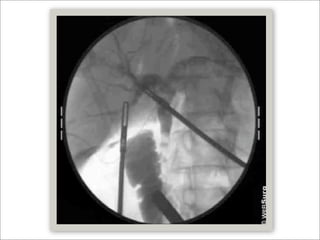

Colangiografía intraoperatoria

   Altamente sensible (95%)

   A favor

   Colédocolitiasis no sospechadas 1 to 14 % (promedio 5%) en pacientes de bajo riesgo

cuando se utiliza IOC de rutina

   Puede prevenir lesión de VB (identificación de anatomía)

Colangiografía intraoperatoria  Altamente sensible (95%)  A favor  Colédocolitiasis no sospechadas 1 to 14 % (promedio 5%) en pacientes de bajo riesgo cuando se utiliza IOC de rutina  Puede prevenir lesión de VB (identificación de anatomía)  Bagnato VJ,. Justification for routine cholangiography during laparoscopic cholecystectomy. Surg Laparosc Endosc 1991;1:89-93.  En contra  Falsos positivos (0.6 – 6%, promedio 3.1%)  Qué tan factible es realizar canulación de cístico por laparoscopía?  Del 90-99%  Garzon J et al. Cholecystectomy without operative cholangiography. Implications for common bile duct injury and retained common bile duct stones. Ann Surg 1993;218:371-7; discussion 377-9